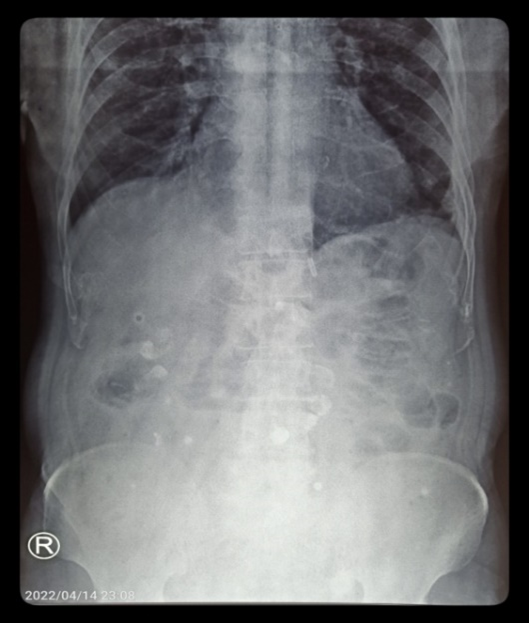

An abdominal erect x-ray was taken and surprisingly it showed multiple hyperdense foci in multiple quadrants in of abdomen (Figure 2). The patient became asymptomatic after one day of conservative management by keeping nil per oral and intravenous analgesics. Ultrasound of the abdomen revealed only bilateral raised renal echoes and there was no evidence of solid organ injury.

Figure 2: Multiple hyperdense foci in multiple quadrants of abdomen.